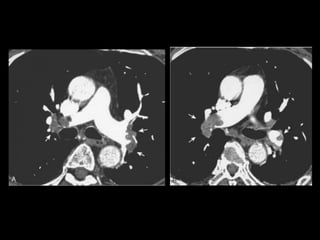

• 62.

Embolia Pulmonar Diagnóstico deembolia aguda na TC com contraste é baseado na visualização direta de falhas de enchimento parciais ou completas dentro das artérias pulmonares; Sinal da “rosca”; Sinal do “trilho de trem”; Outro sinal útil: formação de ângulos agudos com a parede vascular, a perda completa da opacificação e o aumento do diâmetro do vaso acometido.

• 70.

Embolia Pulmonar Tromboscrônicos: com frequência aparecem como defeitos de enchimento em forma de crescente ou laminares aderidos às paredes da artéria pulmonar; Calcificações podem estar presentes; Armadilhas: tempo de delay, volume de contraste, sangue não opacificado oriundo da veia cava inferior e do átrio direito( interrupção transitória de contraste);